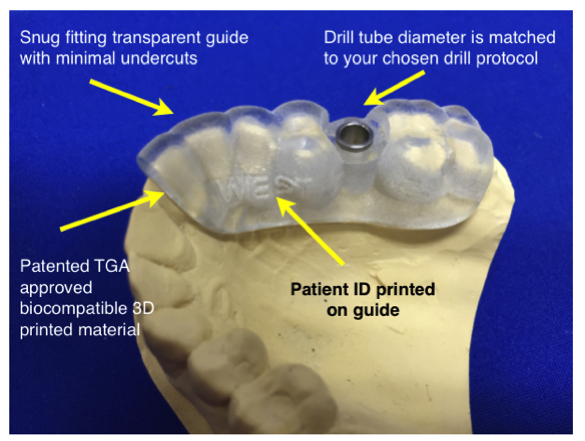

5. Guide fabrication

We use state of the art FDA and TGA approved, fully tested and calibrated 3D printing machines and materials for our surgical guides. You will receive a perfectly fitting sturdy guide with drill tubes precision fitted ready for use. All guides are manufactured in Sydney, Australia at our own dedicated facility so fast turnaround is always guaranteed. Rush orders are usually not an issue.

We will supply a drill guide with drill tubes suitable for your selected type of guide.

We can also supply genuine implant manufacturers drill tubes when requested.

Anatomy of an Implaguide